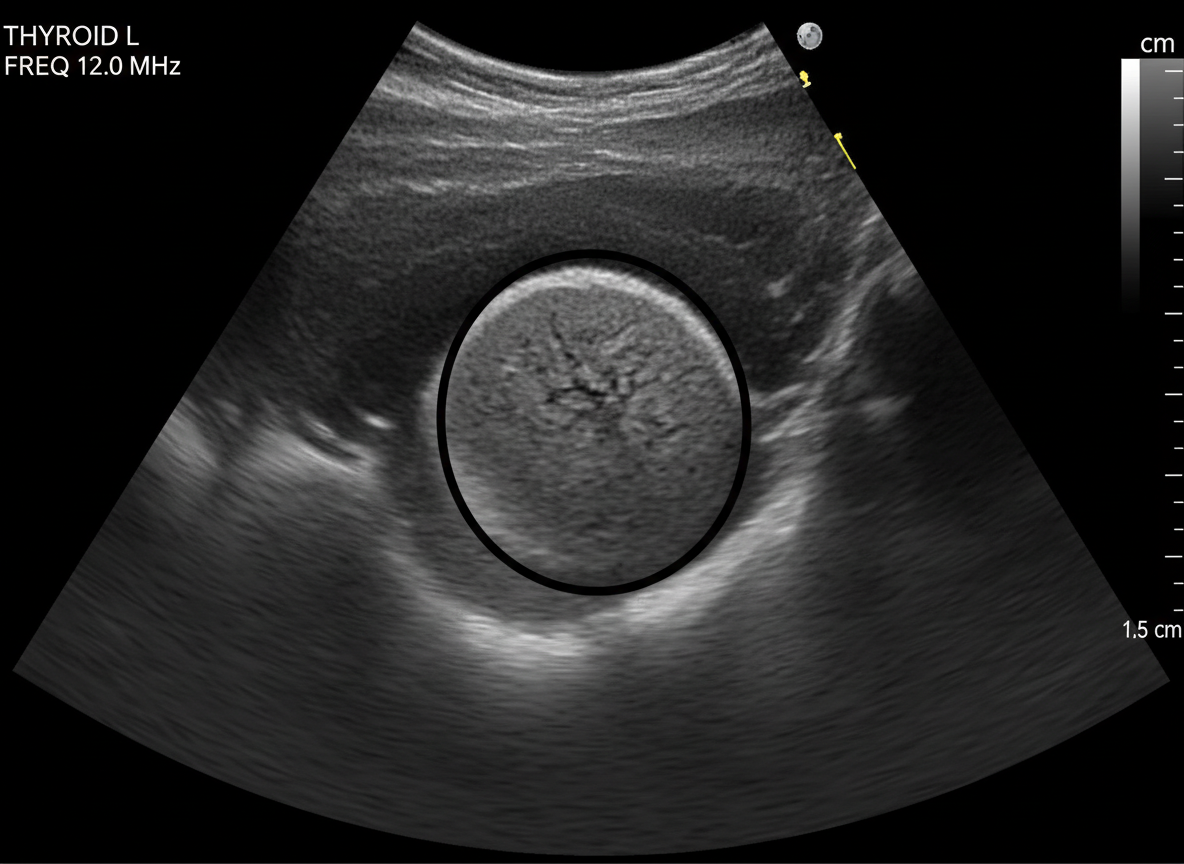

그 다음으로는 갑상선 초음파 검사를 하게 되는데,

이 초음파 검사를 통해

갑상선 결절의 유무와 크기, 모양 등을 확인할 수 있답니다.

초음파는 통증도 없고 아주 간단한 검사라서

부담 없이 받으실 수 있을 거예요.

만약 초음파 검사에서

의심스러운 결절이 발견된다면,

초음파 검사로 간단하게 확인할 수 있으니,

절대 망설이지 마세요!